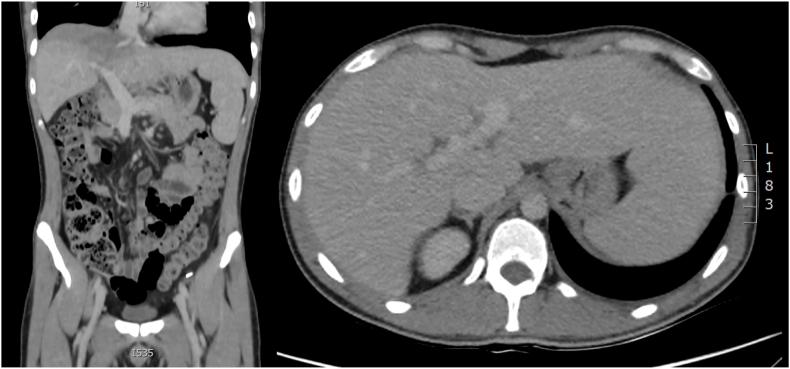

We present the unique case of a patient who was diagnosed with an actinomycotic liver abscess after coronavirus disease 2019 (COVID-19) without the presence of any chronic disease or mucosal injury.

According to the results of the computer tomography (CT scan) and the liver biopsy, the patient was treated with antibiotics and ultrasound-guided drainage.

我们呈现了一例独特病例,该患者在感染2019冠状病毒病(COVID-19)后被诊断出患有放线菌性肝脓肿,且不存在任何慢性疾病或黏膜损伤。

根据计算机断层扫描(CT扫描)结果和肝活检结果,该患者接受了抗生素治疗及超声引导下引流。